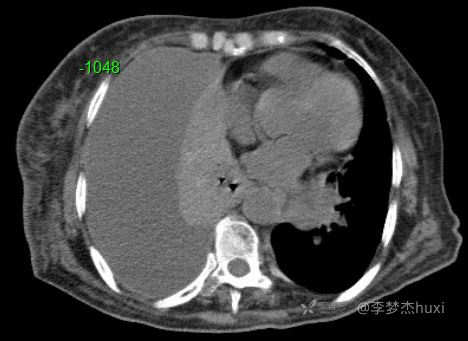

女性78岁,右侧满罐胸水,你绞尽脑汁也想不到的原因

临床诊断:右侧胸腔积液